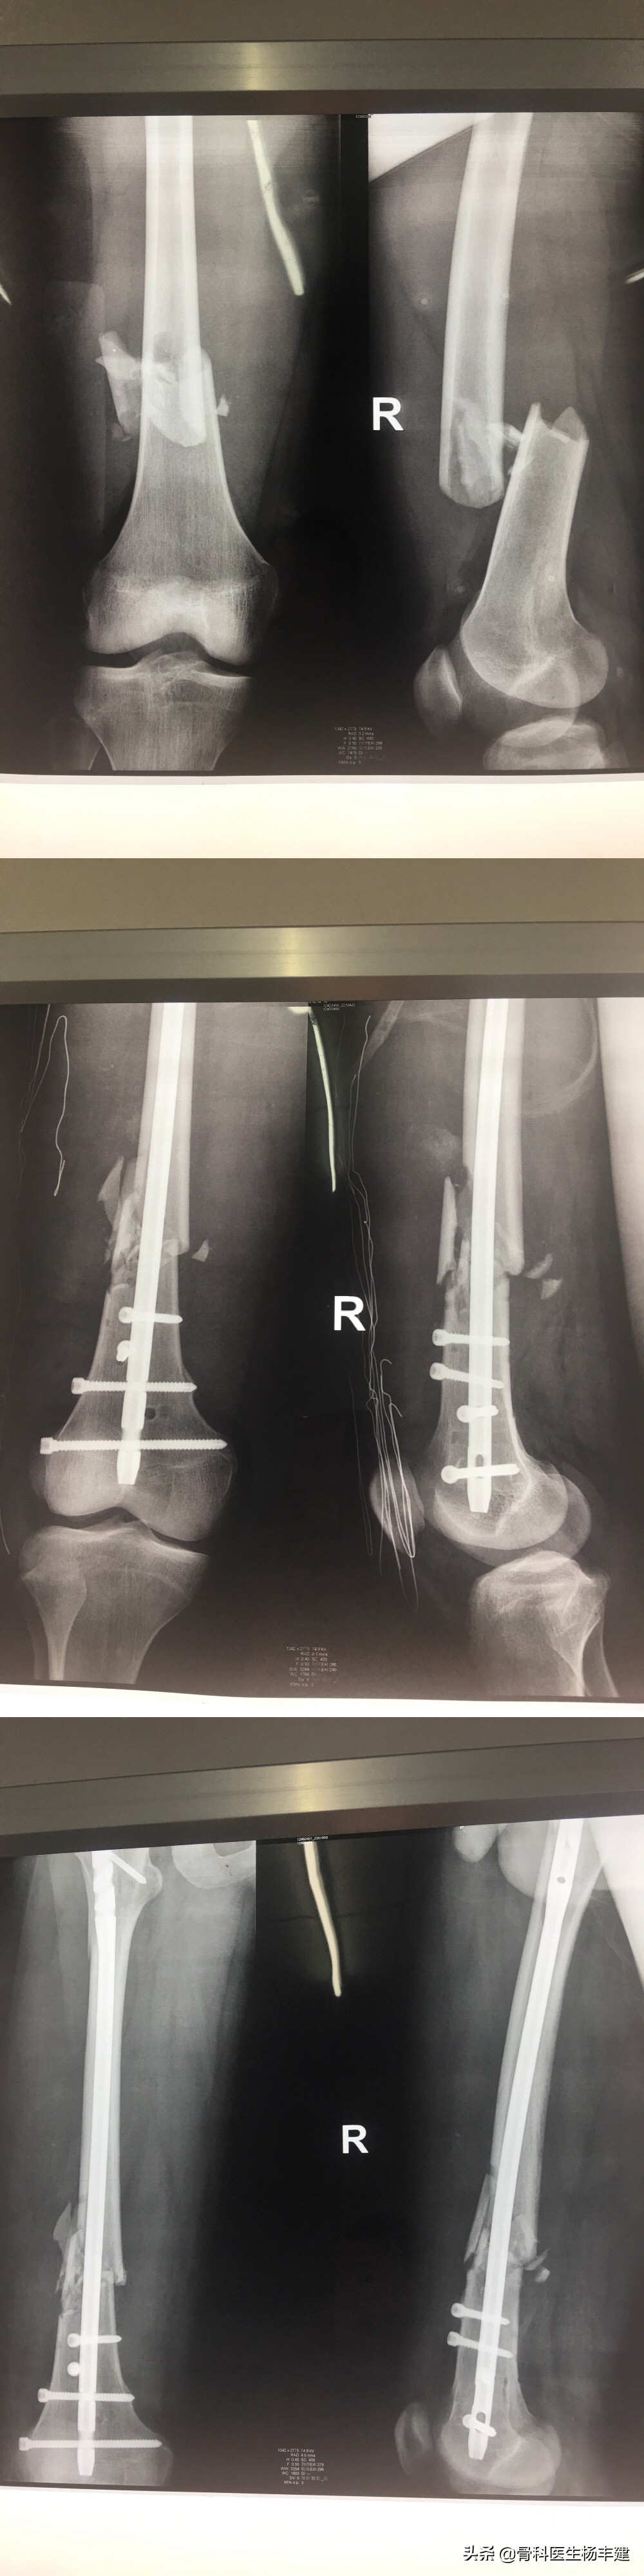

随着微创技术,以及内固定设计的进步,目前越来越多的干部骨折采用闭合复位,或者不直接在骨折部位切开的方法进行治疗。只要手术中纠正了力线、旋转和成角的移位,骨折愈合过程中,会对周围的骨片和侧方的错位进行一定程度的自我纠正。下图是一个股骨干部骨折的19岁病人,使用髓内钉固定后,前方的骨折片有一定程度的移位,但是在骨折后6周,骨片的位置明显改善。

股骨干部骨折采用闭合复位的典型例子,从上至下分别是手术前、手术后,手术后6周